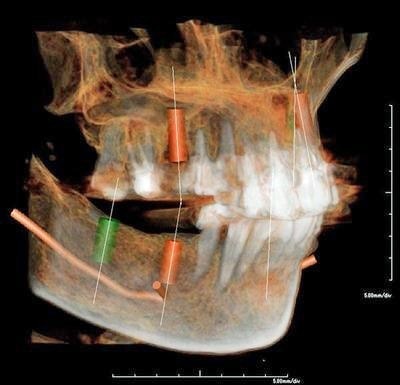

レントゲンでは把握できないことまでCTでは確認することが出来ます。

身体を断面や立体図として見ることができ、骨はもちろんの事、神経や血管に至るまで確認することができます。

そのデータを元に、どのような角度、どのような深さでインプラントを打ち込むかなど、的確な治療計画を立てることができます。